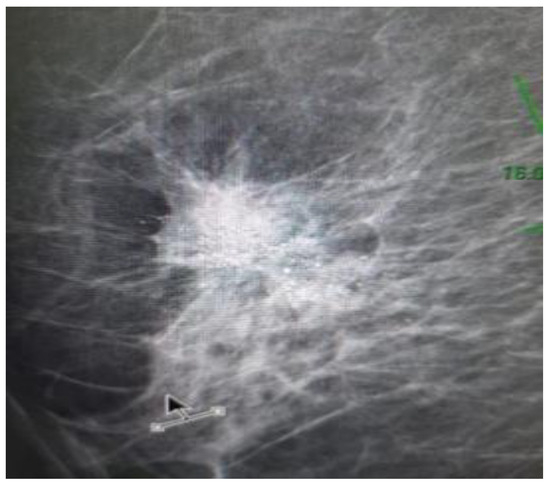

A mammography (Figure 1) was performed, showing an irregular opacity with spiculiform contour in the supero-external dial of the right breast. The maximum diameter of the lesion was 18/16 mm, and multiple microcalcifications (over 30) were observed. The next step was the ultrasound guided biopsy of the breast. At this moment, the possibility of having two different tumors at the same time was also included in the differential diagnosis.

As well as the clinical presentation, the radiologic characteristics are also unspecific and similar to the other malignant breast lesions. In a mini review article, Gallo et al. summarized the imaging characteristics of breast NEC, reported in case reports or small series: the most common mammographic appearance is a hyperdense, irregularly shaped solitary mass; margins are more commonly reported as indistinct, micro-lobulated or speculated. In most cases, calcifications are absent [12,13,14]. Taking into account the most common mammographic appearance described by Gallo et al., it is important to remember that multiple microcalcifications were observed in this case.

Figure 1. Mammography of the right breast: irregular opacity with spiculiform contour in the supero-external dial with a maximum diameter of 18/16mm, and multiple microcalcifications.